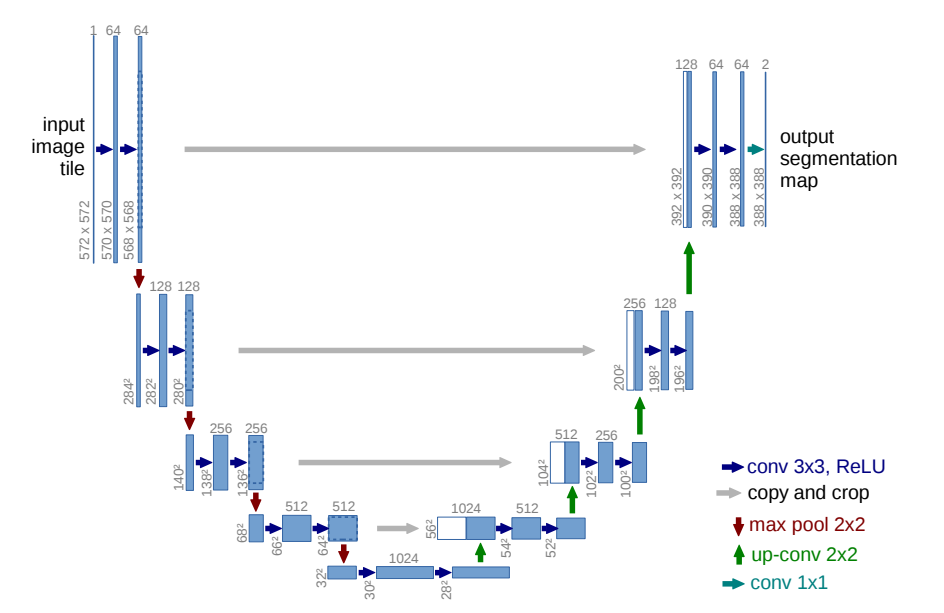

U-Net 是一种经典的用于医学图像分割的卷积神经网络(CNN)架构。它的设计初衷是为了解决医学图像中复杂目标(如肿瘤、器官等)的精确分割问题。U-Net 通过对称的编码器和解码器结构,结合跳跃连接(skip connections),实现了在分割任务中高效的特征提取和精细的空间恢复。

U-Net 的网络结构分为两个主要部分:编码器(下采样部分)和解码器(上采样部分)。编码器部分通常由一系列卷积层和池化层组成,目的是逐步提取图像中的抽象特征并降低空间分辨率。每个卷积层后面跟随一个非线性激活函数(通常是ReLU),用于增强模型的非线性表达能力。池化层(如最大池化)则用于降低空间分辨率并减少计算量。

解码器部分通过上采样逐步恢复图像的空间分辨率。上采样通常通过反卷积层(或转置卷积)实现,目的是将低分辨率的特征图恢复到原始图像的尺寸。解码器中的关键设计是跳跃连接,具体来说,U-Net 会将编码器各层提取的特征图直接传递到解码器对应层进行融合。这种跳跃连接保证了解码器能够使用来自编码器的高分辨率特征,帮助恢复图像的细节,特别是在分割物体的边界部分。

最终,U-Net 使用一个 1x1 的卷积层将解码器的输出映射到所需的分割类别数,生成像素级的分割结果。为了获得更精确的分割结果,输出通常通过一个 Sigmoid(用于二分类)或 Softmax(用于多分类)激活函数进行处理。

U-Net 的优势在于它能够在进行高效特征提取的同时,保留图像中的细节信息,尤其适用于需要精确分割边界的医学图像。通过跳跃连接,U-Net 可以有效地融合来自浅层和深层的特征,使得模型既能捕捉图像的全局语义信息,又不丢失细粒度的局部信息。这使得 U-Net 成为了医学图像分割领域中最常用的深度学习架构之一。